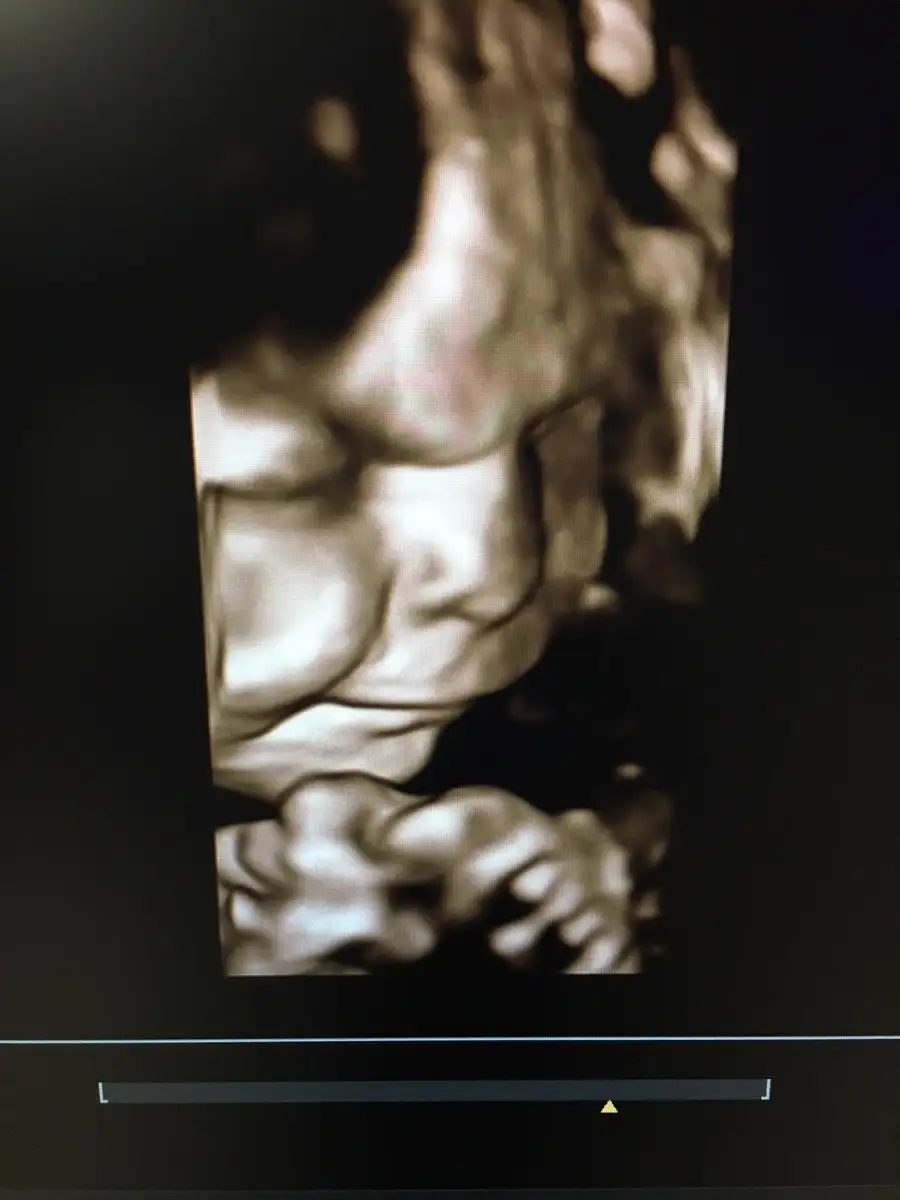

Doğum öncesi son günler için ve doğum sırasında yapabileceklerim için öneriler var mı :) ebeleri yorup üzmeden en kolay şekilde nasıl doğurabilirim?

Doğumdan nerdeyse hiç korkmuyorum nedense, endişelenmeli miyim?